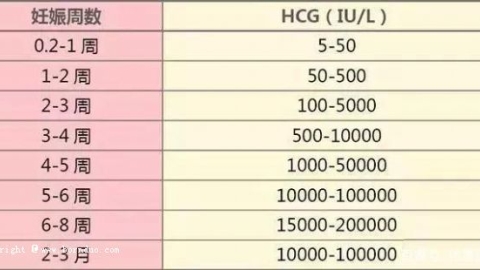

通常是建议患者在胚胎移植后14天后,到医院抽血检查是否怀孕。如果是试管婴儿囊胚移植的话,在植入后10天可抽血确认是否有怀孕。由于第三代试管婴儿囊胚移植成功率较高,所以对于双胚胎移植的情况来说,双胞胎的...